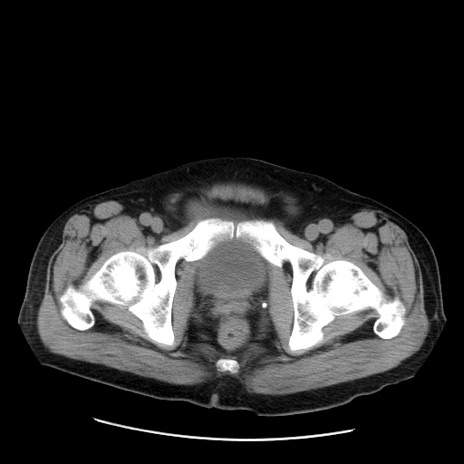

症例20(横断像)

【症例】 60歳代男性

【主訴】 腹部膨満、嘔吐

【現病歴】5日前頃より倦怠感を認め食事量減少し4日前の朝嘔吐、食事摂取困難となった。 3日前近医受診し点滴施行され整腸剤などを処方された。 当日他院を受診し、腹部膨満著明、炎症反応の上昇(CRP10.8、WBC11200)あり、紹介受診となる。

【身体所見】 意識JCS1 受け答えがはっきりしないBP 111/57mHg、 P 67bpm、、BT35.2°C、SpO2 97%(RA)、 腹部:膨隆、打診で鼓音あり、全体的に圧痛有り、腸蠕動音(-)、反跳痛ははっきりせず。

【データ】WBC 11400、CRP 14.20